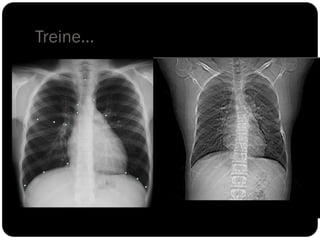

Treine...

Treine: